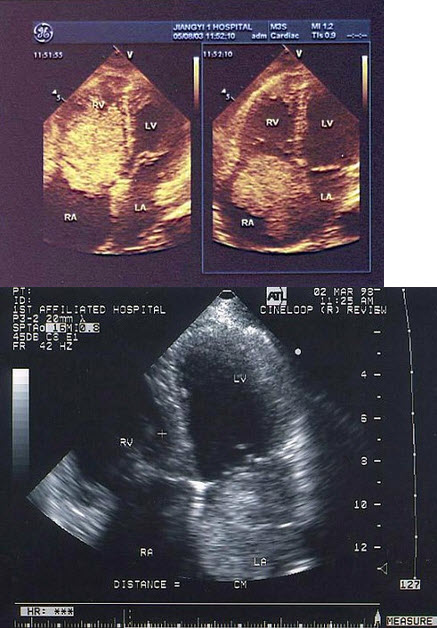

51、单项选择题

该食管超声心动图显示图像为()

A.房间隔缺损(上腔型)

B.房间隔缺损(下腔型)

C.房间隔缺损(中央型)

D.房间隔缺损(混合型)

E.冠状静脉窦扩张

某患者左室长轴切面超声心动图如图所示,诊断为()

A.正常声像图

B.主动脉瓣关闭不全

C.二尖瓣关闭不全

D.室间隔缺损

E.房间隔缺损

80、单项选择题 患者感心悸、胸闷,过去无心脏病史,最可能诊断()

A.冠心病

B.扩张型心肌病

D.主动脉瓣关闭不全

E.肥厚性心肌病